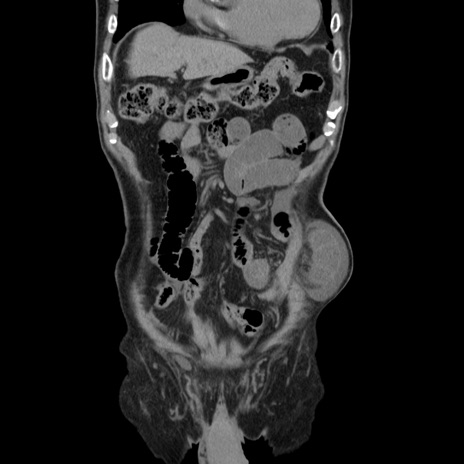

症例24(冠状断像)

【症例】80歳代男性

【主訴】左側腹部痛、嘔吐

【現病歴】本日早朝より左腹部に痛みあり。昼頃嘔吐認めたため、救急要請。

【既往歴】直腸癌(Mile手術)、胆摘

【身体所見】意識清明、BT 35.9℃、BP 221/93mmHg、SpO2 97%(RA) 、腹部:左ストーマ周囲に限局性の腹部膨隆あり。 膨隆部自発痛・圧痛あり・軟。

【データ】WBC 7700、CRP 0.09